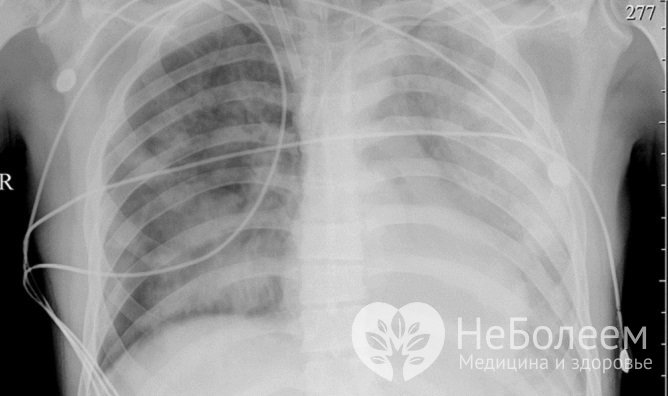

Наиболее серьезным проявлением аденовирусной инфекции у детей и взрослых является аденовирусная пневмония. Обычно она возникает на 3-5 сутки болезни, только у детей первых лет жизни аденовирусная инфекция может сразу манифестировать воспалительным процессом в легочной ткани. Симптомами аденовирусной пневмонии являются:

Аденовирусная пневмония может быть как мелкоочаговой, так и сливной, то есть охватывающей одновременно несколько сегментов легких.

Опасным осложнением аденовирусной инфекции является аденовирусная пневмония – на рентгенографииУ детей первых трех лет жизни аденовирусная пневмония нередко принимает тяжелое течение и сопровождается появлением пятнисто-папулезной кожной сыпи, формированием очагов некроза в коже, головном мозге и легких.